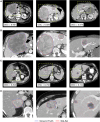

Liver tumors, whether primary or metastatic, significantly impact the outcomes of patients with cancer. Accurate identification and quantification are crucial for effective patient management, including precise diagnosis, prognosis, and therapy evaluation. We present SALSA (system for automatic liver tumor segmentation and detection), a fully automated tool for liver tumor detection and delineation. Developed on 1,598 computed tomography (CT) scans and 4,908 liver tumors, SALSA demonstrates superior accuracy in tumor identification and volume quantification, outperforming state-of-the-art models and inter-reader agreement among expert radiologists. SALSA achieves a patient-wise detection precision of 99.65%, and 81.72% at lesion level, in the external validation cohorts. Additionally, it exhibits good overlap, achieving a dice similarity coefficient (DSC) of 0.760, outperforming both state-of-the-art and the inter-radiologist assessment. SALSA's automatic quantification of tumor volume proves to have prognostic value across various solid tumors (p = 0.028). SALSA's robust capabilities position it as a potential medical device for automatic cancer detection, staging, and response evaluation.